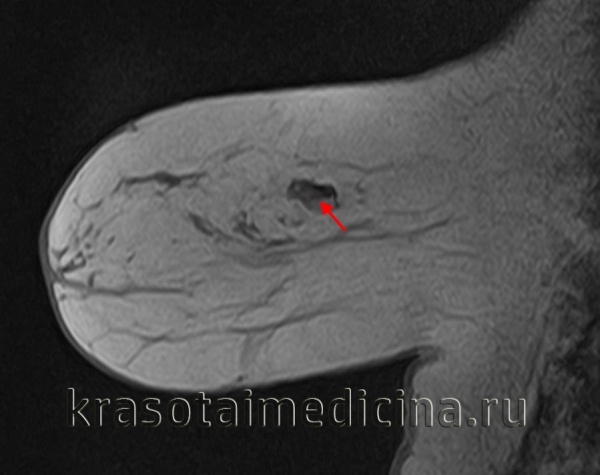

МРТ молочных желез. Подтвержденная фиброаденома молочной железы.